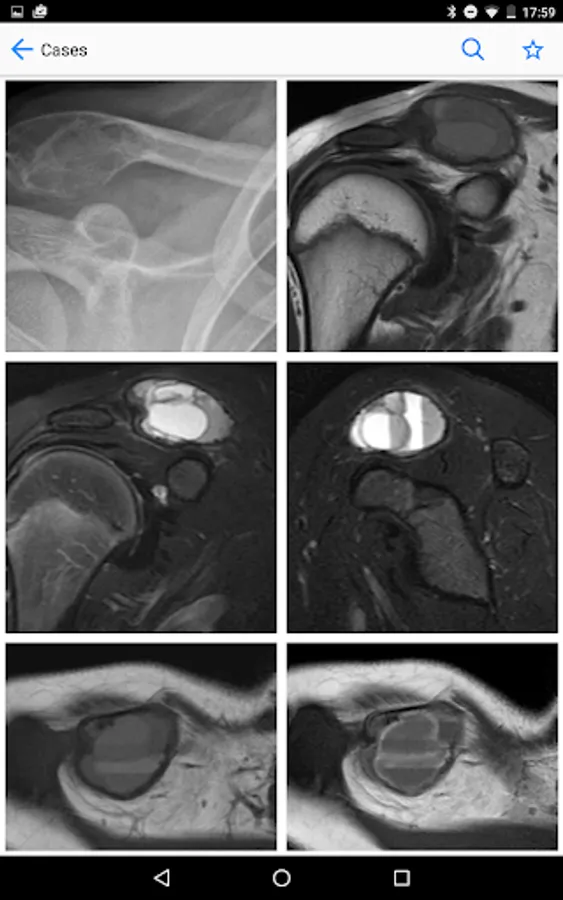

BoSTT brings the user a real experience of frequent and rare, typical and more unusual cases of bone and soft tissue tumours. Each case has a clinical history, high resolution radiology and pathology images, diagnosis, treatment and learning points.